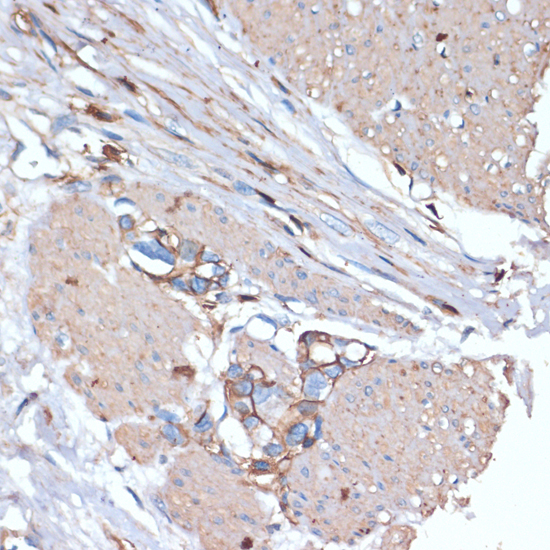

Immunohistochemistry of paraffin-embedded human tonsil using CD44 at dilution of 1:200 (40x lens).

Immunohistochemistry of paraffin-embedded human colon carcinoma using CD44 at dilution of 1:200 (40x lens).

Immunohistochemistry of paraffin-embedded human gastric cancer using CD44 at dilution of 1:200 (40x lens).